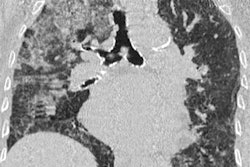

Gamechi and colleagues thus developed a technique for automatically segmenting and measuring the thoracic aorta on noncontrast CT scans. Although several segmentation techniques exist that enable clinicians to collect aortic measurements automatically, they are mostly limited to use with contrast-enhanced imaging such as coronary CT angiography, according to the authors.

The researchers' automatic segmentation technique combines multiple image-processing steps, including a multiatlas registration algorithm, to localize and segment the aorta and major arteries on 3D CT scans. Then it calculates the average aortic diameter based on measurements from 13 cross-sectional slices taken at fixed intervals with respect to a single anatomical landmark.